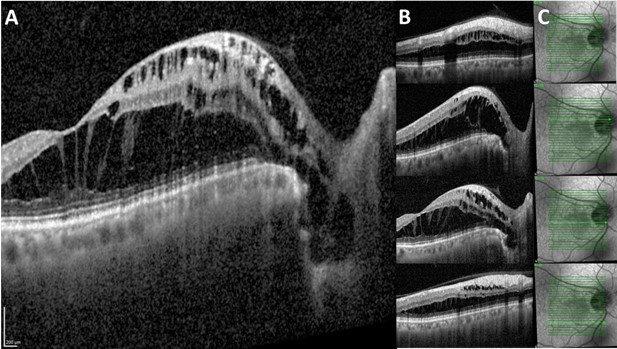

Fig 3. OCT at different sections of patient’s optic disc pit maculopathy. A) The fovea and the disc displaying the

hyporeflective space extending from the base of the optic nerve head and throughout the retina, causing separation of

multiple retinal layers. C) En face infrared reflectance with light-green arrow corresponding with the marker in B

A 58-year-old male with no underlying medical history was referred for retinal oedema adjacent to the optic nerve head with cystic changes and a shiny appearance on the overlying retina for the right eye. Unaided visual acuity was 6/9 and 6/6. He was asymptomatic and was incidentally noted to have macula oedema during a routine examination. The anterior segment examination was normal, but the right eye optic disc assessment showed a greyish-white depressed area in the temporal quadrant (Figs 1 and 2) along with cystic changes at the macula. The left eye examination was normal. OCT examination of the right eye showed schisis-like separation of retinal layers, most marked in the outer retinal layers, extending up to the optic disc temporal margins (Fig 3). There appeared to be a clear communication between the optic disc and the schisis-like separation of outer retinal layers.

Clinically, ODP usually appears as a greyish-whitish, round or oval depression of the optic disc (Fig 1), and it may have different levels of severity. More than half of the patients in their third or fourth decade go on to develop maculopathy. Typically, OCT demonstrates fluid in the sub-retinal and intra-retinal compartments. The outer retinal layers are more commonly affected and the OCT demonstrates schisis-like separation of the outer retinal layers. Very often, schisis-like separation of the retinal layers extends to the optic disc pit, as seen in this case.